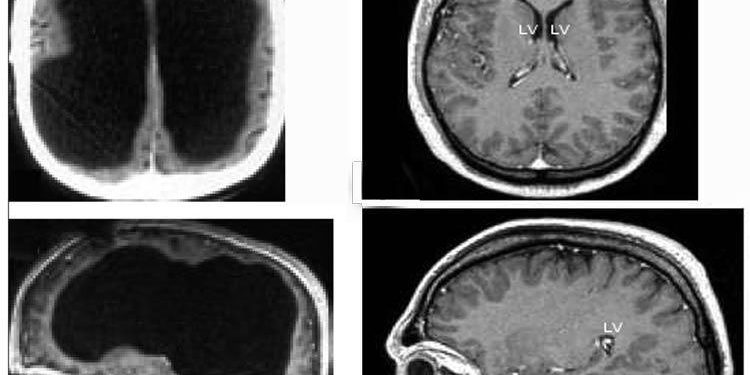

Сканирование мозга мужчине сделали практически случайно. Он пришёл в больницу с жалобой на слабость в левой ноге, но врач направил его на томограмму. Результаты МРТ показали, что череп мужчины практически полностью заполнен жидкостью. Остался только тонкий внешний слой с мозговым веществом, а внутренняя часть мозга практически отсутствует.

Учёные считают, что мозг пациента медленно уничтожался в течение 30 лет по мере накопления жидкости — процесс, известный как гидроцефалия (водянка головного мозга). Ему поставили такой диагноз ещё в подростковом возрасте и провели шунтирование для восстановления движения ликворной жидкости, но в 14 лет шунт убрали. С тех пор жидкость в черепе накапливалась, а мозг постепенно уничтожался.